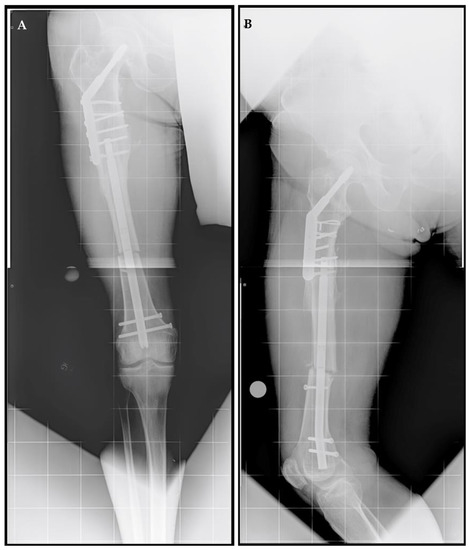

A 71-year-old male, an avid skier and cyclist with a history of sports-related injuries, was referred for LLD. He suffered a right femur fracture at age 53 that required femoral IM nail fixation. He also experienced a right intertrochanteric femur fracture at age 67, for which he underwent sliding screw fixation. He walked with a half-inch heel lift inside his right shoe. He had been experiencing lower back and right knee pain for more than three years prior to initial presentation. He stated that he did not want to wear shoe lifts for the rest of his life and found it difficult to maintain an active lifestyle. The patient also had a history of prostate cancer and coronary artery bypass surgery, both of which had been treated successfully. He no longer experienced cardiac symptoms. Upon physical examination, he demonstrated right femoral retroversion with a slight pelvic tilt with compensation noted. There was a femoral discrepancy (right side shorter than left) of approximately 2 cm when performing the Galeazzi test. Radiographs showed mild osteopenia with plate and screw fixation of the proximal right femur in the area of the intertrochanteric fracture, with mature bone callus formation. A 3.0 cm femoral discrepancy was measured, with the right side shorter than left side (Figure 1).

Figure 1.

Posttraumatic femoral lengthening in a 71-year-old male patient, shown preoperatively. (A) Anteroposterior bilateral long leg and (B) right long leg lateral prior to the insertion of the Precice MILN. Gray dots on the bottom represent X-ray calibration spheres.